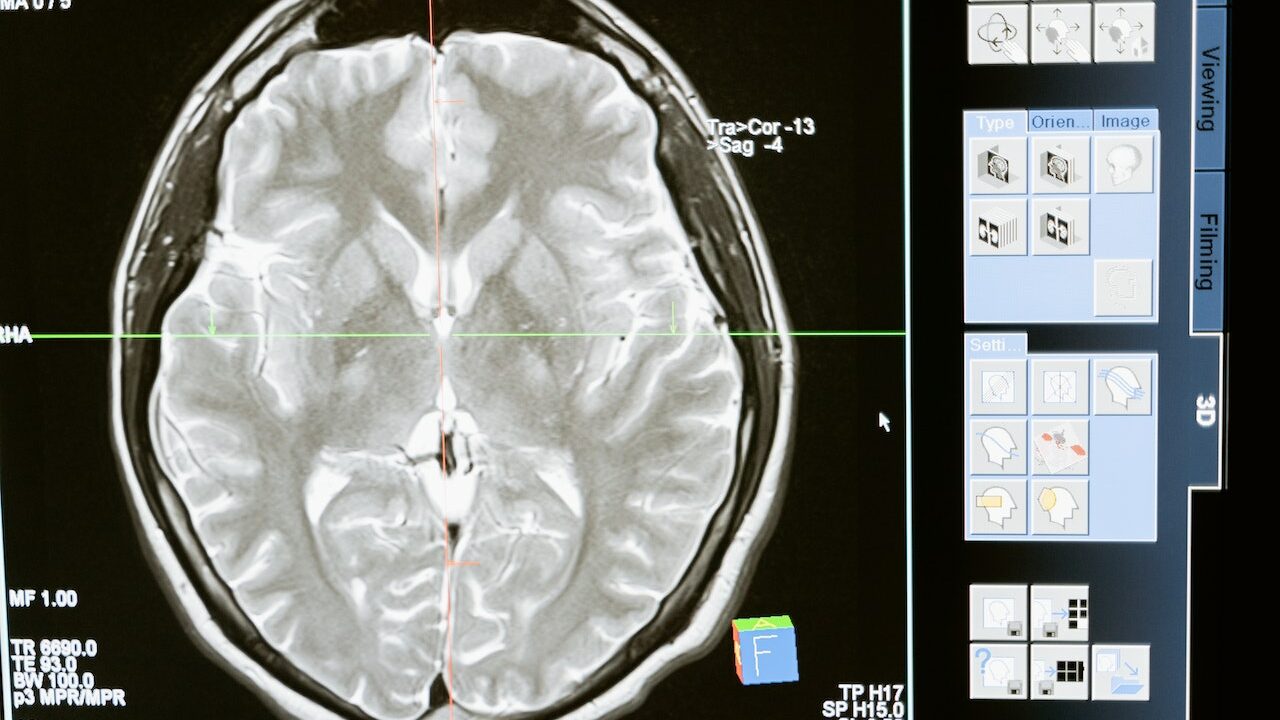

- Ультразвукове дослідження нирок дає змогу візуалізувати стан і аномалії органів.

- У деяких випадках для більш детального обстеження уролог призначає комп’ютерну томографію (КТ).